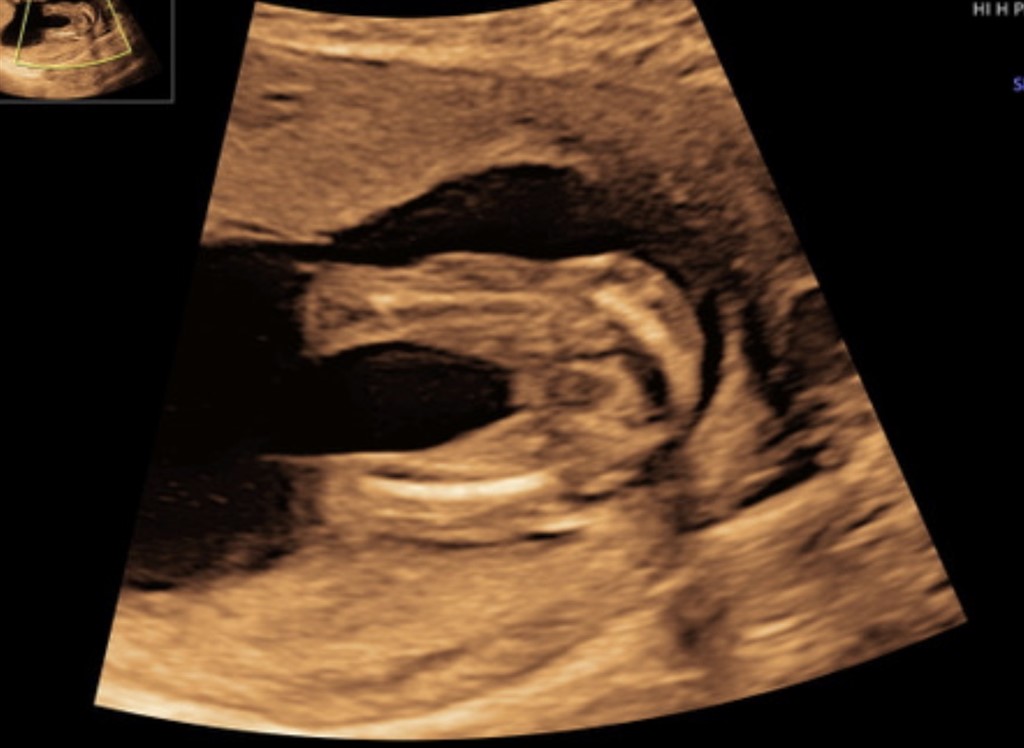

Er der nogen, som kan tyde på disse billeder, at det er en pige?

Jeg skylder lidt forhistorie, beklager. Jeg var til kønsscanning og hun oplyste, at hun var usikker, men troede, at det var en pige. Så blev jeg pludselig selv i tvivl og ville derfor forhøre mig hos jer :-)

Jeg synes det er ok tydeligt med de tre streger for en pige  Tillykke